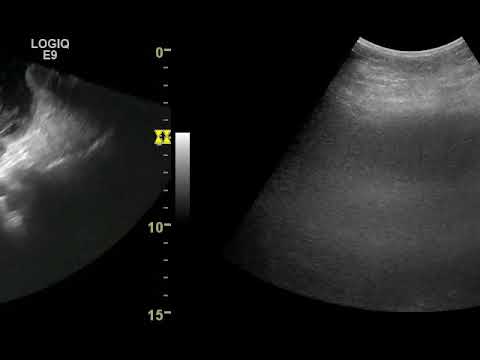

Объемное образование яичника может быть обнаружено врачом при осмотре, однако диагноз кисты устанавливается при ультразвуковом исследовании. По тем или иным ультразвуковым признакам можно с определенной вероятностью предположить тот или иной тип кисты яичника.

Поскольку длительное время киста яичника может себя никак не проявлять, важно регулярно проводить профилактические осмотры у гинеколога. Диагноз кисты яичника довольно легко выставить при гинекологическом осмотре и ультразвуковом исследовании (УЗИ) органов малого таза. УЗИ позволяет не только обнаружить сам факт наличия кисты яичника, но и рассмотреть ее строение (количество камер, характер содержимого, пристеночные включения и разрастания).

Ультразвуковое исследование органов малого таза — самый информативный метод, так как позволяет не только определить наличие кисты, но и наблюдать за ее развитием, оценить ее размеры и структуру.